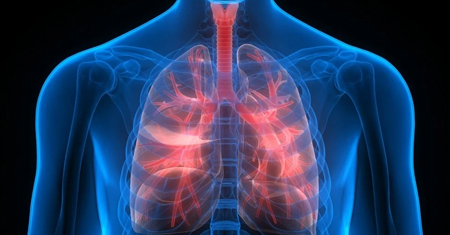

At Pulmocare Clinic,

our mission is to deliver compassionate, cutting-edge pulmonary care that enhances

the quality of life for our patients.

We offer a comprehensive range of advanced pulmonary treatments tailored to meet the unique needs of each patient.